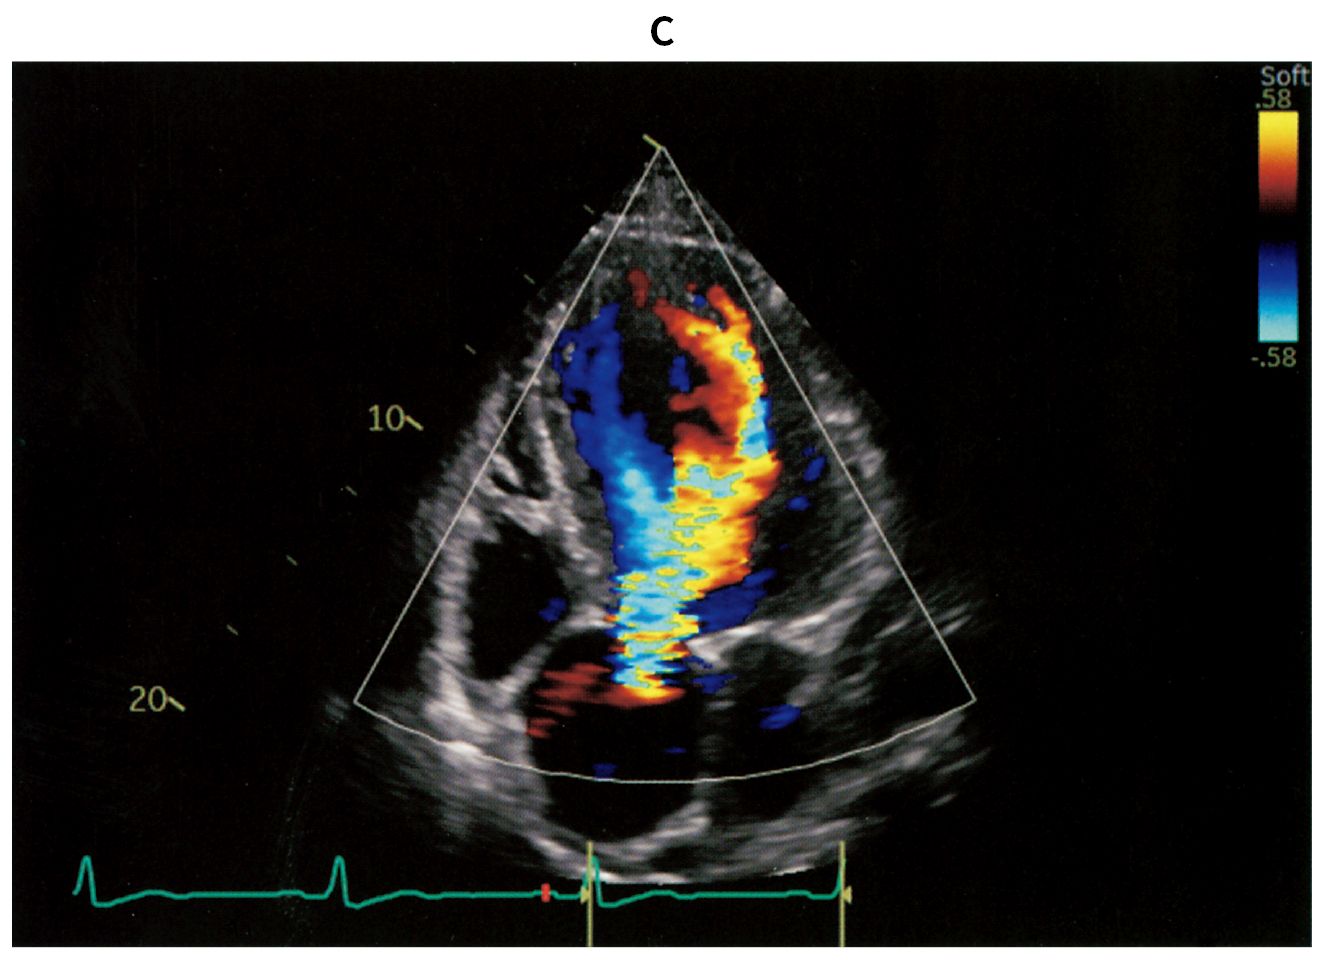

76歳の男性。定期受診で来院した。3年前に拡張期心雑音を指摘され,定期的に心エコー検査で経過観察をしてきた。今回,6か月ぶりの心エコー検査と定期外来で受診し,労作時の息切れを認めた。意識は清明。身長168cm,体重72kg。体温35.8℃。脈拍72/分,整。血圧142/46mmHg。SpO2 98%(room air)。頸静脈の怒張を認めず,呼吸音に異常を認めない。胸骨左縁第3~4肋間にLevine 2/6の拡張期雑音を認める。腹部は平坦,軟で,肝・脾を触知しない。四肢に浮腫を認めない。血液生化学所見:尿素窒素14mg/dL,クレアチニン0.8mg/dL,血糖106mg/dL,HbA1c 6.4%(基準4.9~6.0),BNP 245pg/mL(基準18.4以下)。胸部エックス線写真(A)を示す。心電図では,V4~V6胸部誘導で高電位を認める。心エコー図(B)とカラードプラ心エコー図(C)とを下に示す。心エコー検査では,左室拡張期径69mm,左室駆出率46%,大動脈弁輪の拡大と重症の大動脈弁閉鎖不全症を認める。胸部造影CTでも,著明な大動脈弁基部の拡張を認める。冠動脈造影検査で冠動脈に病変を認めなかった。